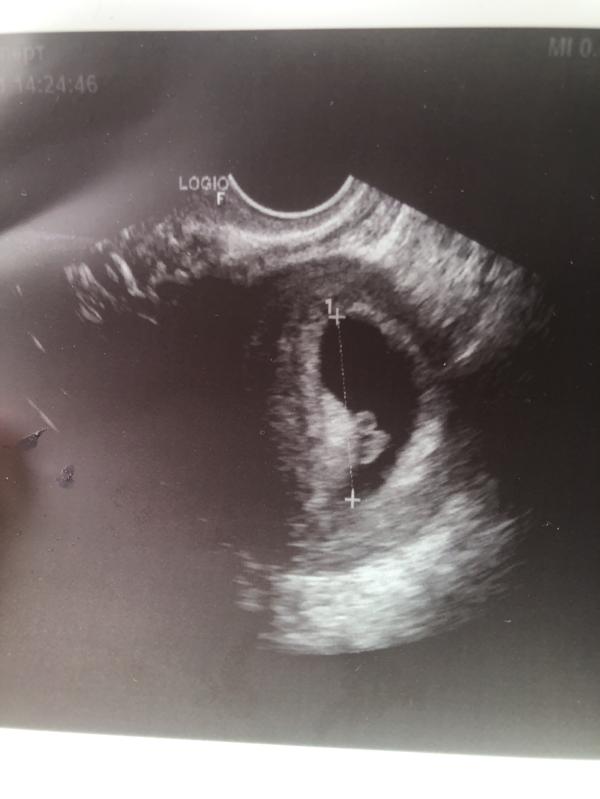

Девочки, здравствуйте, сейчас у меня 7 недель и 5 дней. Была на узи, сказали гипертонус . Но меня ничего не беспокоит от слова совсем ! Стоит ли переживать? Врачи пугают , говорят что судьба решит быть или не быть

Если нет боли и выделений, то все в норме. Первую беременность его видели и эту тоже на УЗИ. Меня не беспокоит. Матка мышечный орган, имеет свойство периодически сокращаться.